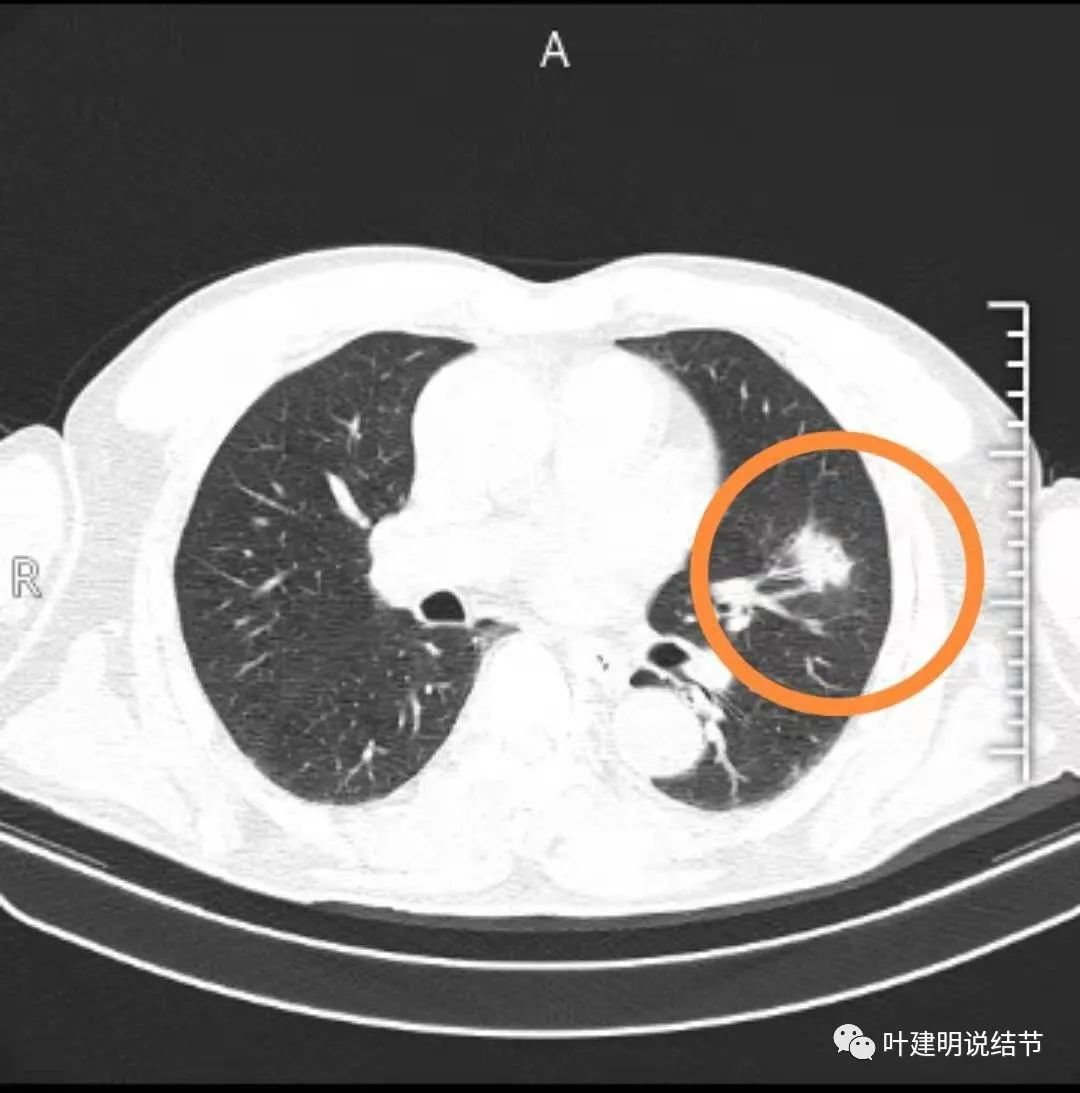

有分叶征,有毛刺等恶性征象就一定是肺癌吗?

实性肺结节的恶性征象,跟混合磨玻璃结节有很多重叠: 1,分叶毛刺 2